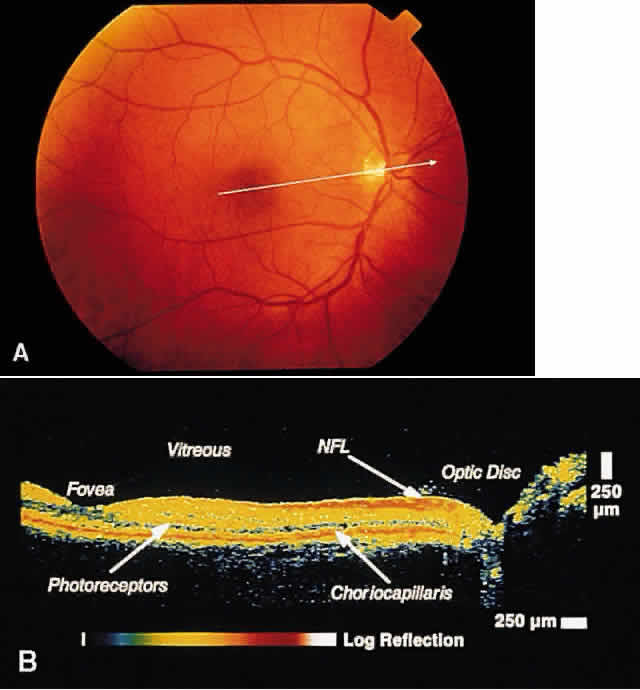

RETINA Central Serous Chorioretinopathy Central serous chorioretinopathy (CSCR) is characterized by detachment(s) of

the neurosensory retina caused by one or more focal leaks at the

level of the RPE. When small or shallow, these serous detachments may

be difficult to detect clinically. OCT images of such areas demonstrate

elevation of neurosensory retina by the presence of subretinal fluid.12 The well-defined contrast in optical reflectivity between the nonreflective

serous fluid and the more highly reflective posterior boundary of

the neurosensory retina allows OCT images to be highly sensitive to

even small neurosensory detachments. Indeed, OCT images may show the presence

of neurosensory detachments not detectable by clinical examination. The

ability of OCT to image the same retinal area on subsequent

visits allows for the longitudinal monitoring of the clinical course of

the serous detachment in this disease (Figs. 2 and 3). OCT is particularly useful when thisdisease presents in older patients. The